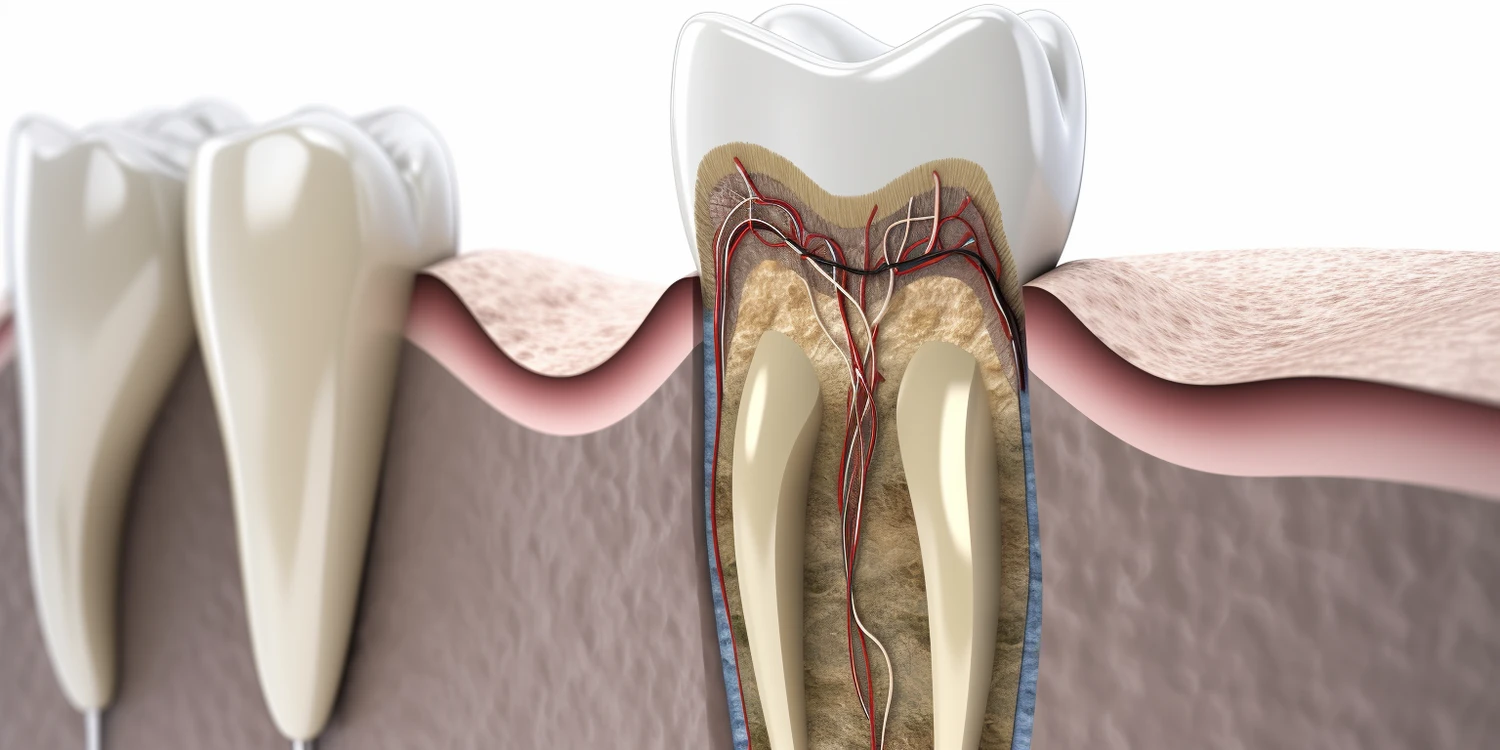

Podczas regularnych wizyt u dentysty można zidentyfikować wiele powszechnych problemów stomatologicznych, które mogą wpłynąć na zdrowie jamy ustnej. Jednym z najczęściej występujących problemów jest próchnica, która rozwija się w wyniku działania bakterii na powierzchni zębów. Dentysta może wykryć wczesne oznaki próchnicy podczas rutynowego badania, co pozwala na szybkie podjęcie działań, takich jak leczenie ubytków czy zastosowanie lakierów fluorowych. Kolejnym istotnym problemem są choroby dziąseł, takie jak zapalenie dziąseł czy paradontoza, które mogą prowadzić do utraty zębów, jeśli nie zostaną odpowiednio leczone. W trakcie wizyty dentysta oceni stan dziąseł oraz ich reakcję na bodźce mechaniczne, co pomoże w diagnozowaniu ewentualnych schorzeń. Dodatkowo, podczas wizyt można również wykryć inne problemy, takie jak zgrzytanie zębami, które może prowadzić do uszkodzenia szkliwa oraz bólu stawów skroniowo-żuchwowych.